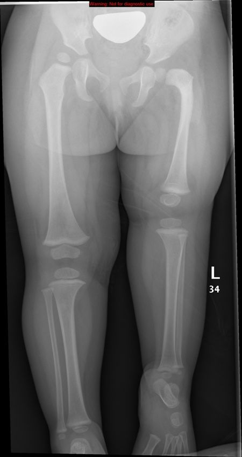

- Conventional Radiography

- Primary diagnostic tool: AP pelvis and lower limb X-rays -bone shortening, abnormal femoral neck orientation, and acetabular changes.?

- Classic features:

- Shortened, sometimes transverse or horizontally placed proximal femoral shaft

- Coxa vara with neck-shaft angle <120°

- Dysplastic or absent acetabulum in higher-grade cases (Aitken classification)

- Comparison with contralateral side for symmetry and severity

Proximal focal femoral deficiency (PFFD) is radiologically classified into types using the Aitken classification.

Bilateral Proximal focal femoral deficiency (class B on right side and class C on left side).